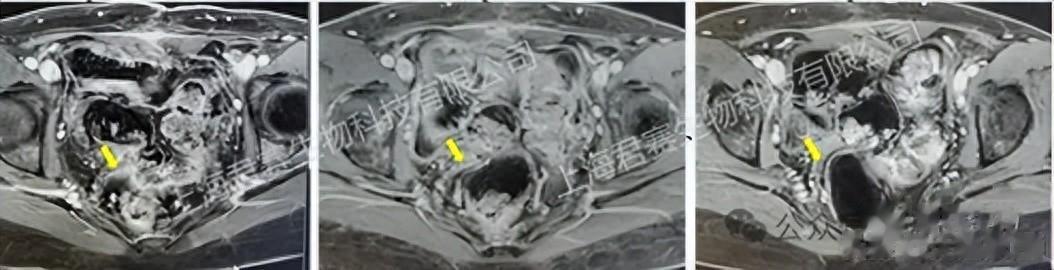

令她难以置信的是,仅仅在接受TIL细胞单次回输两个多月后,检查指标就显示肿瘤病灶完全消失,达到完全缓解(CR)。如今,四年过去了,她依然健康地生活着,回归了正常工作和生活。

受试者接受TIL回输前、回输后6周及回输后12周影像资料(图源官网,侵删)